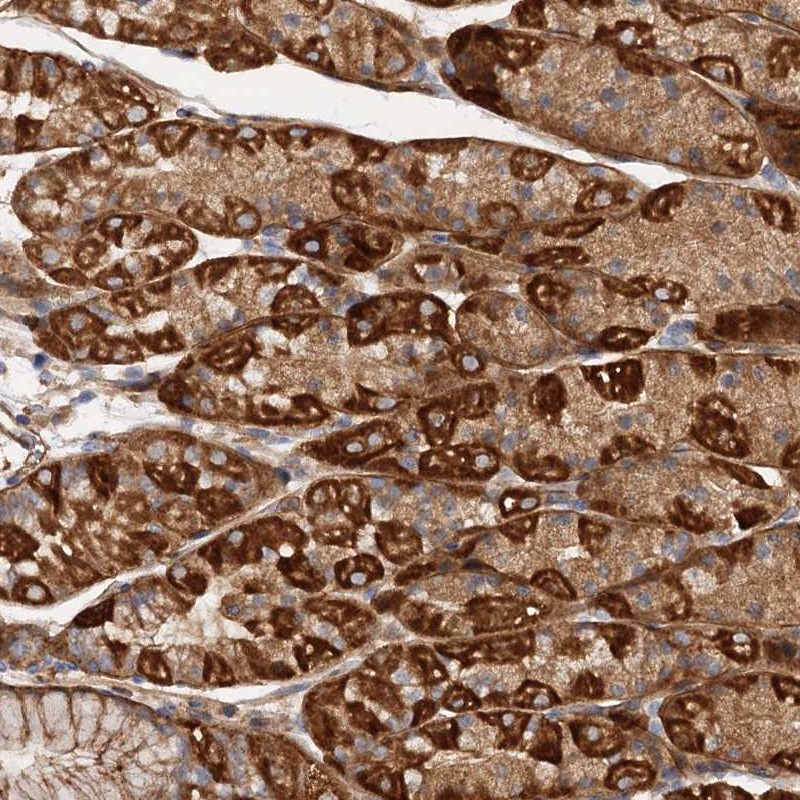

Immunohistochemical staining of human stomach shows strong cytoplasmic positivity in glandular cells.